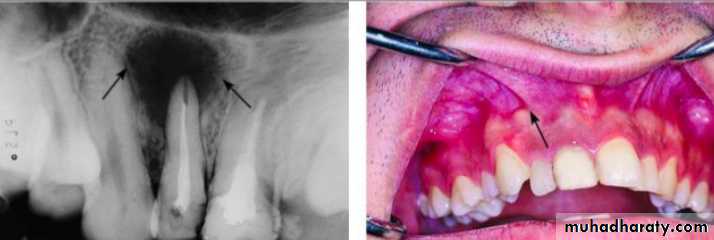

5. Periradicular abscess

An Inflammatory reaction to pulpal infection that can be chronic or have rapid onset with pain, tenderness of the tooth to pressure, pus formation, and swelling of the tissues.

6. Periodontal abscess.

An inflammatory reaction frequently caused by bacteria entrapped in the periodontal sulcus .A patient will experience rapid onset, pain, tenderness of the tooth to pressure , pus formation, and swelling.

7. Periradicular cyst

A cyst that develops at or near the root of a necrotic tooth. These types of cysts develop as an inflammatory response to pulpal infection and necrosis of the pulp.8. Pulp fibrosis

7- Surgical endodontic

Indication for surgical intervention

Endodontic failure caused by persistent infection, severely curved roots ,perforation of the canal, pulp stones, or accessory canals that cannot be treated.Exploratory surgery

To determine why healing has not occurred